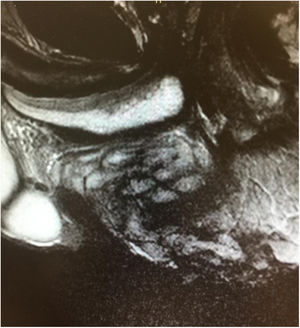

On MRI (Fig. 2), alteration of the perineal fat was observed in the form of fibrous tracts that protruded towards the perineum. The treatment of choice is excision. This highlights the importance of clinical suspicion based on a correct anamnesis.